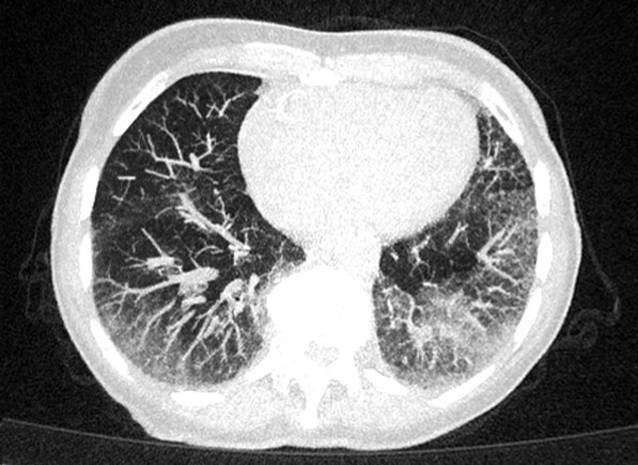

In der Computertomographie des Thorax fielen bilaterale Milchglastrübungen und subpleurale, basale Retikulationen als Ausdruck einer interstitiellen Lungenerkrankung („Indeterminate usual interstitial pneumonia“[UIP]-Muster) (vgl. Abb. 1) auf. Passend hierzu zeigte die Lungenfunktionsuntersuchung eine eingeschränkte forcierte Vitalkapazität (FVC 50 %, FEV1/VC 69 %). Bei hochgradigem Verdacht auf eine muskuläre Beteiligung im Rahmen einer entzündlichen Systemerkrankung erfolgte eine Magnetresonanztomographie der Oberschenkel mit Nachweis T2-hyperintenser Veränderungen der Oberschenkelmuskulatur mit geringerer Signalanhebung des M. rectus femoris beidseits (vgl. Abb. 2). Zur weiteren ätiologischen Einordnung der muskulären Beteiligung erfolgte eine Biopsie des M. vastus lateralis links. Histopathologisch waren myopathische Aspekte mit deutlicher Kalibervarianz der Muskelfasern neben diffus-endomysialen Infiltraten von autoinvasiven T‑Zellen darstellbar. Neben einer Überexpression von MHC-Klasse I und II waren zahlreiche Cytochrom-C-Oxidase(COX)-negative Muskelfasern ohne geräderte Vakuolen darstellbar, entsprechend einer Polymyositis mit mitochondrialer Pathologie (PM-Mito) (vgl. Abb. 3).

Abb. 1

Low-dose-Computertomographie des Thorax. Bilaterale Milchglastrübungen und basale, subpleural betonte Retikulationen als Ausdruck einer interstitiellen Lungenerkrankung, radiologisch als „indeterminate UIP“ („usual interstitial pneumonia“) gewertet